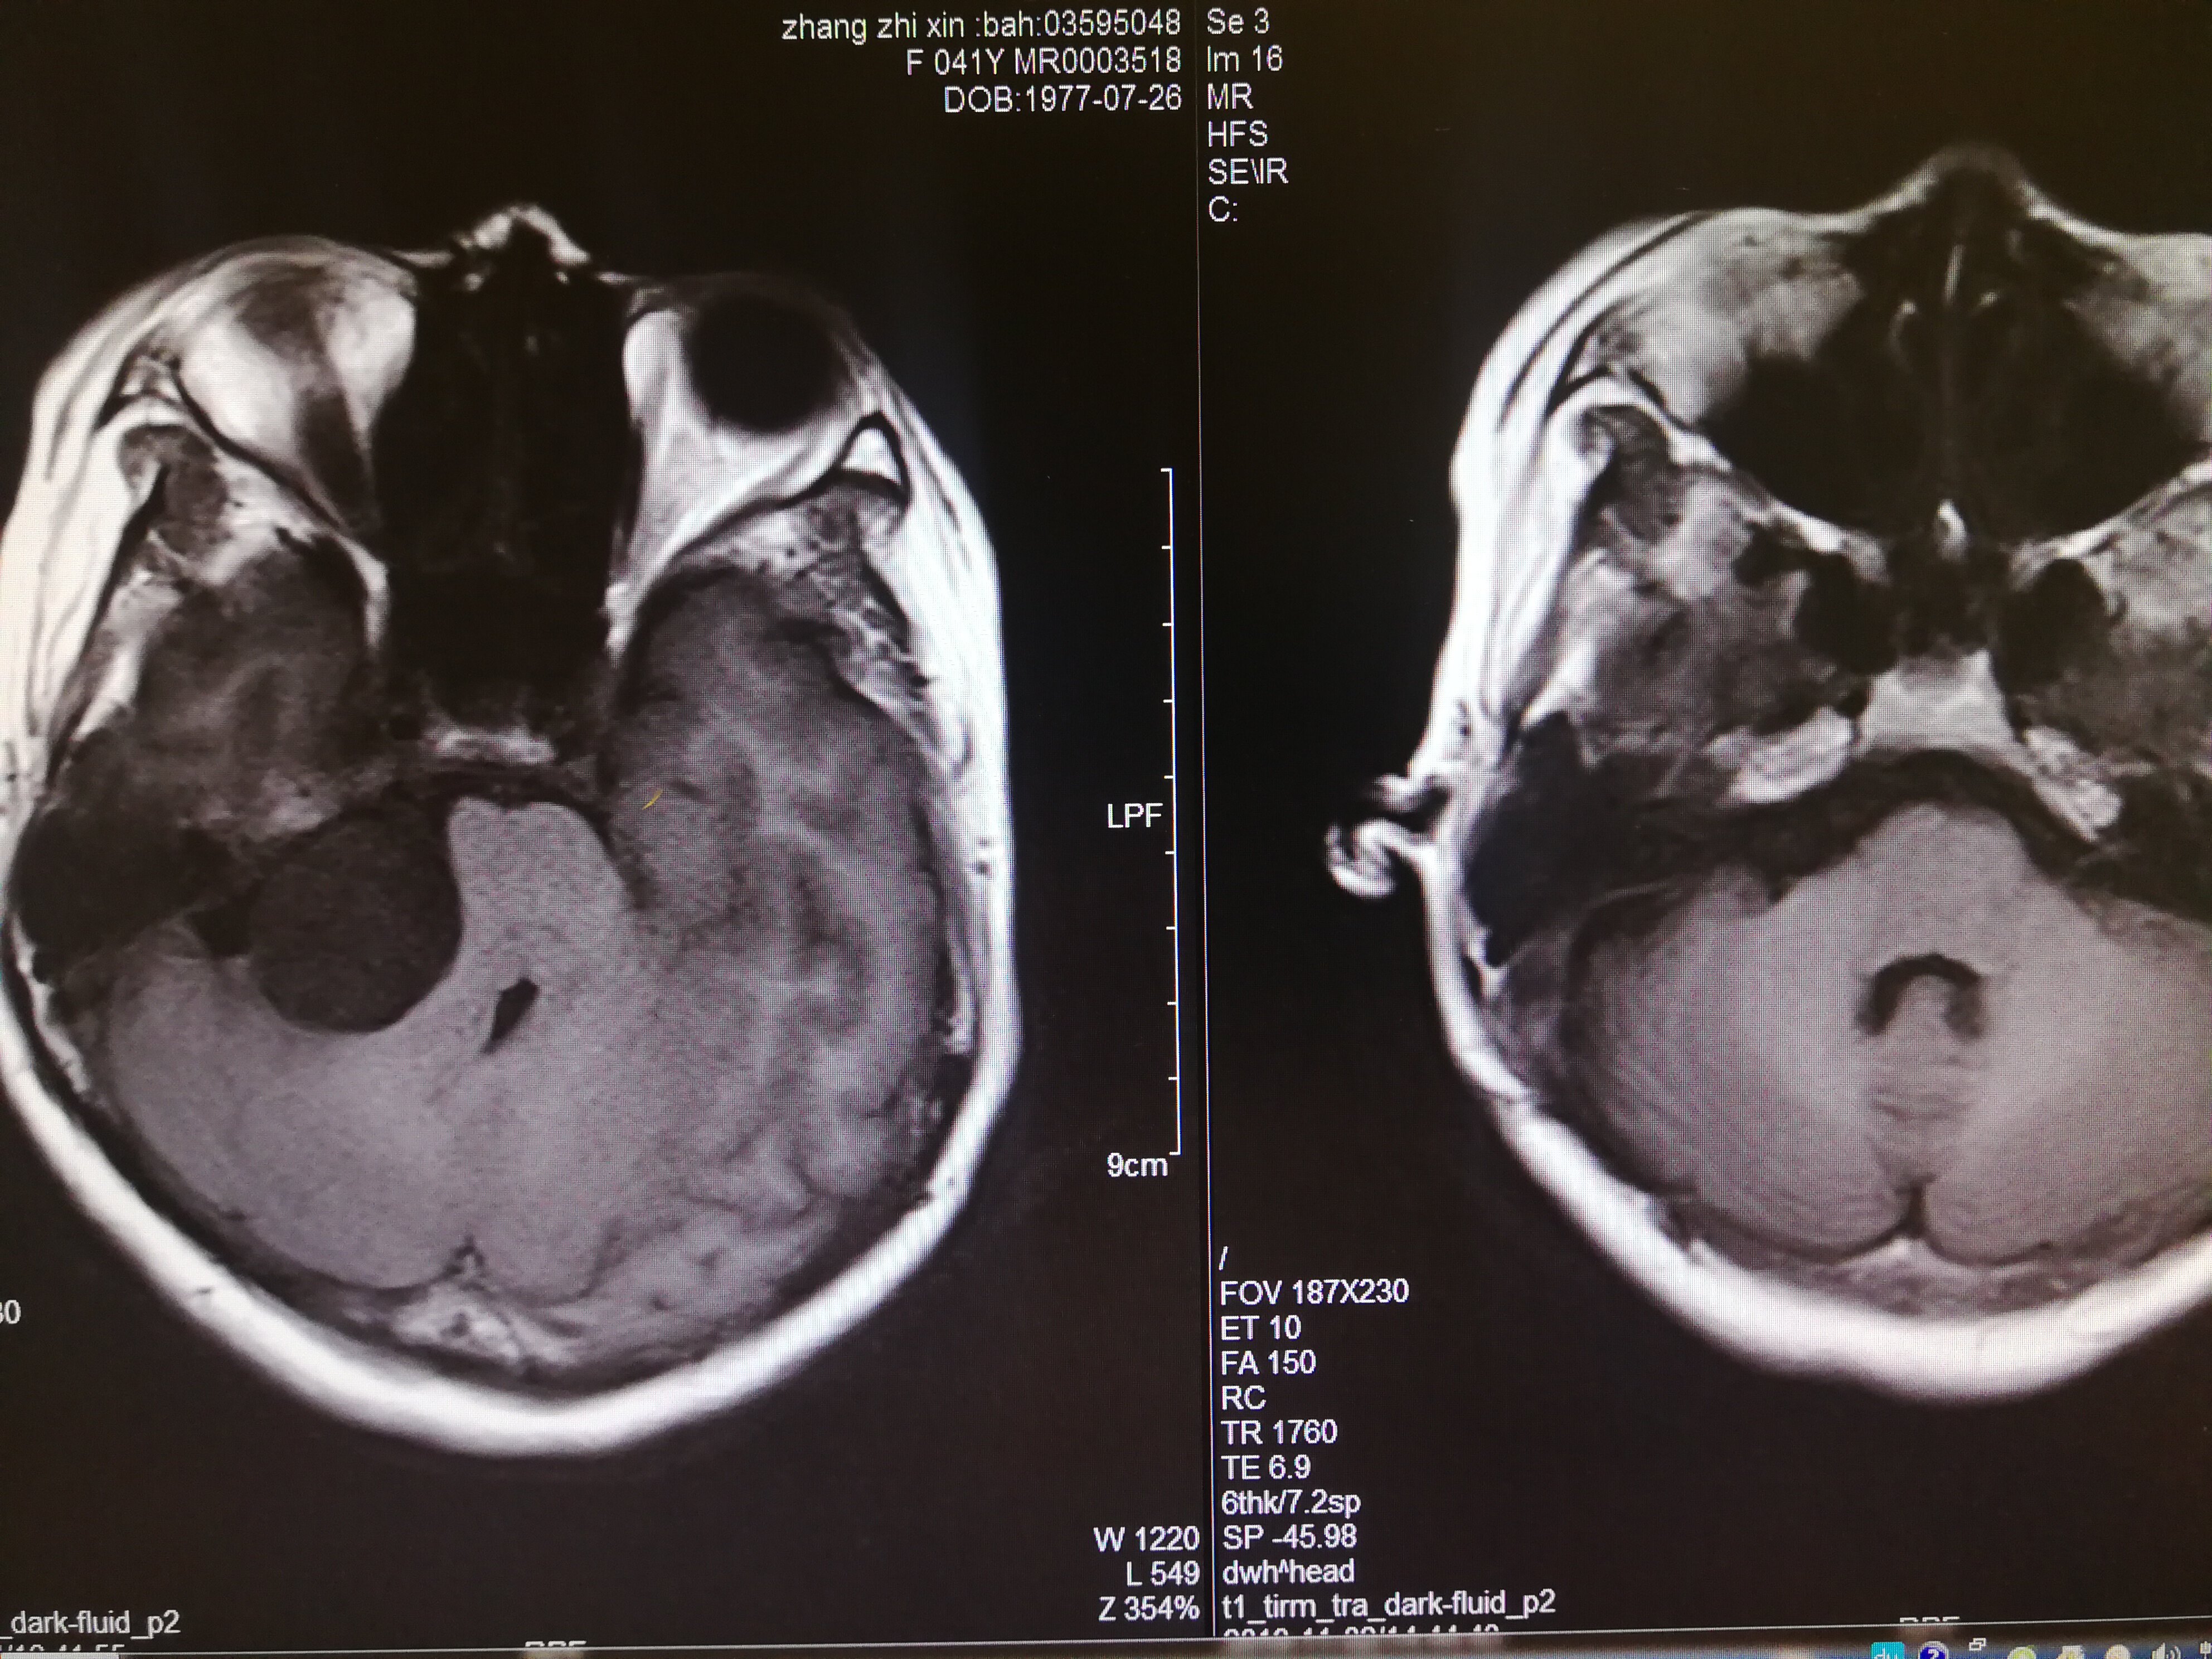

手术治疗听神经瘤是最主要的治疗方式,目前听神经瘤的手术已经非常成熟,只要没有明显的手术禁忌症首先应考虑手术治疗,并要求在电生理监测条件下完成手术,这样可以最大限度地保护面神经功能。以下是几例我们做的听神经鞘瘤手术前后核磁共振片子对照,除手术后听力不能恢复外,没有面瘫,脸部麻木,吞咽困难等颅神经症状,也无其他较明显的手术并发症发生。